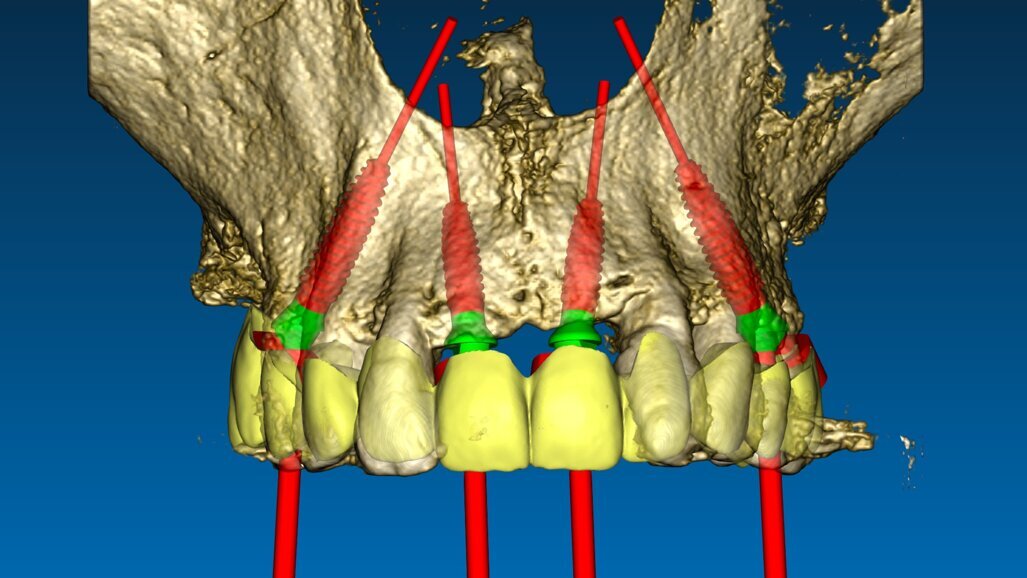

In prima fase, sono state scansionate entrambe le arcate, così da ottenere una registrazione occlusale e una dimensione verticale. Sono state scattate fotografie intra- ed extra-orali con precisi parametri, per visualizzare tutti i dati raccolti in un software di digital smile design. I file STL sono stati poi sovrapposti ai file DICOM della TC Cone Beam con un software dedicato. Tramite un software di chirurgia guidata è stata poi stabilita la posizione dei 4 impianti post-estrattivi, da posizionare con l’ausilio di due dime chirurgiche differenti (Fig. 2). La prima dima ad appoggio dentale è stata prodotta al fine di creare le sedi per l’alloggiamento dei pin di posizione. La seconda dima fissata con pin nella posizione precedentemente determinata, presenta le cannule per la preparazione del sito e l’inserimento implantare (Figg. 3a, 3b). Sulla base della stessa ceratura è stata poi prodotta una protesi totale fissa provvisoria in PMMA rinforzata con una struttura in titanio, su cui è stata riprodotta la dimensione verticale originaria del paziente.

Fig. 2_Progetto digitale per il posizionamento di 4 impianti mono componente post estrattivi: si evidenzia la pianificazione protesicamente guidata grazie ad una ceratura virtuale.